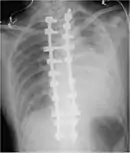

Chest X-ray

A chest X-ray is the most common technique used to diagnosis a hemothorax.[23] X-rays should ideally be taken in an upright position (an erect chest X-ray), but may be performed with the person lying on their back (supine) if an erect chest X-ray is not feasible. On an erect chest X-ray, a hemothorax is suggested by blunting of the costophrenic angle or partial or complete opacification of the affected half of the thorax. On a supine film the blood tends to layer in the pleural space, but can be appreciated as a haziness of one half of the thorax relative to the other.[5] A small hemothorax may be missed on a chest X-ray as several hundred milliliters of blood can be hidden by the diaphragm and abdominal viscera on an erect film. Supine X-rays are even less sensitive and as much as one liter of blood can be missed on a supine film.[24]